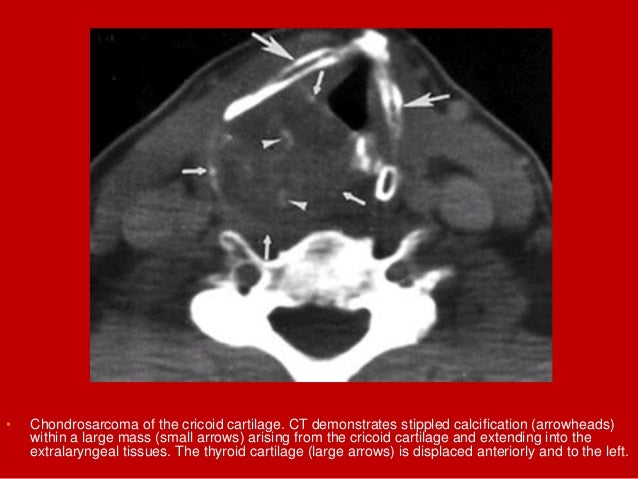

20. 20. Coronal T1Tumour invasion of PGS